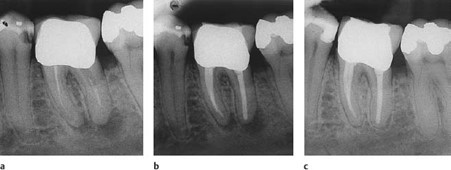

This image shows 4 potential areas where microbes can be post treatment.

1. Intraradicular microbes: if the preparation of the canal is not at its correct length, then microbes will persist at the constriction and spread.

2. Extraradicular microbes: this is when microbes have invaded the host response system and established themselves in the periapical tissues.

3. Foreign body reaction to extruded gutta- percha.

4. True cyst which is cavity that has walled itself off from the root canal system.

1. Intraradicular microbes: if the preparation of the canal is not at its correct length, then microbes will persist at the constriction and spread. 2. Extraradicular microbes: this is when microbes have invaded the host response system and established themselves in the periapical tissues. 3. Foreign body reaction to extruded gutta- percha. 4. True cyst which is cavity that has walled itself off from the root canal system.